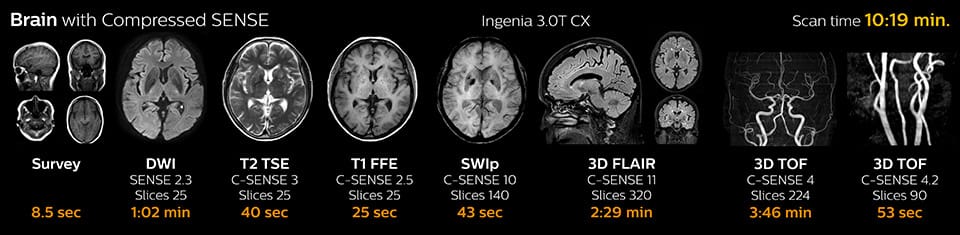

“We now only need about 10 minutes of scan time for a brain exam – and we still get the same amount of images and equal quality. We even managed to make a very useful improvement: we replaced the 43-second T21 FFE by a 43-second SWIp, which is more powerful for us in making confident diagnoses in certain patients.” “SWIp was not previously included in our standard protocol, because of its slightly longer scan time. SWIp provides high resolution 3D susceptibility weighted imaging in the brain, which helps to visualize small deoxygenated blood or calcium deposits. Now, with Compressed SENSE, we can perform 3D SWIp in only 43 seconds, so we have included SWIp instead of the 2D T21 FFE that we used previously. Without adding scan time, we now get SWIp images in every routine brain scan and it helps us increase our diagnostic confidence in certain cases.”

Scanning time reduction in brain MRI with Compressed SENSE

With Compressed SENSE, the scan time for the routine brain examination at KNC was reduced from 15:48 to 10:19 minutes, which corresponds to 35% reduction.

Brain with Compressed SENSE

Ingenia 3.0T CX

Scan time 10:19 min.